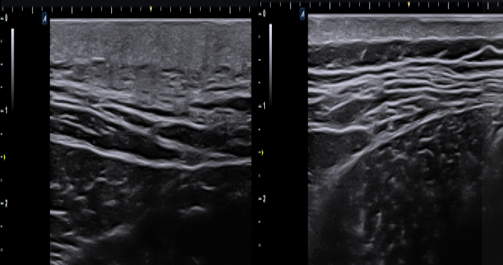

좌측이 환자분 피부 초음파, 우측이 김병균 원장님 피부 초음파 입니다.

– 기립근 부위와 목 어깨 쪽의 피부가 fibrotic change다오고

실제 초음파상의 두께가 2cm정도나됩니다